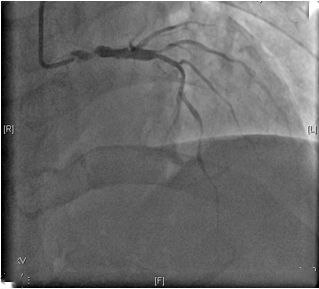

冠脉造影显示狭窄严重

冠脉造影显示心脏的三根主要冠脉均有狭窄,需要进行冠脉搭桥术。冠状动脉是包绕在心脏外,为心脏供给血液和营养的重要动脉,一旦狭窄就会导致胸闷、疼痛及心肌梗塞等,严重者可致死亡。冠脉搭桥术是取患者本身的血管,如乳内动脉、下肢的大隐静脉等,或者血管替代品,将狭窄冠状动脉的远端和主动脉连接起来,让血液绕过狭窄的部分,到达缺血部位,改善心肌血液供应,达到缓解心绞痛症状,改善心脏功能的目的。